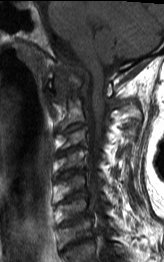

#CaseOfTheWeek‼️🥳‼️ ☢️🩻☠️Case#22☠️🩻☢️ #Mass 📲➡️➡️#Diagnosis❔❓❔ #FOAMRad #RadEd #MedEd #OrthoEd #OrthoTwitter @ssr_rwg @UWRadRes @ISSVA_org